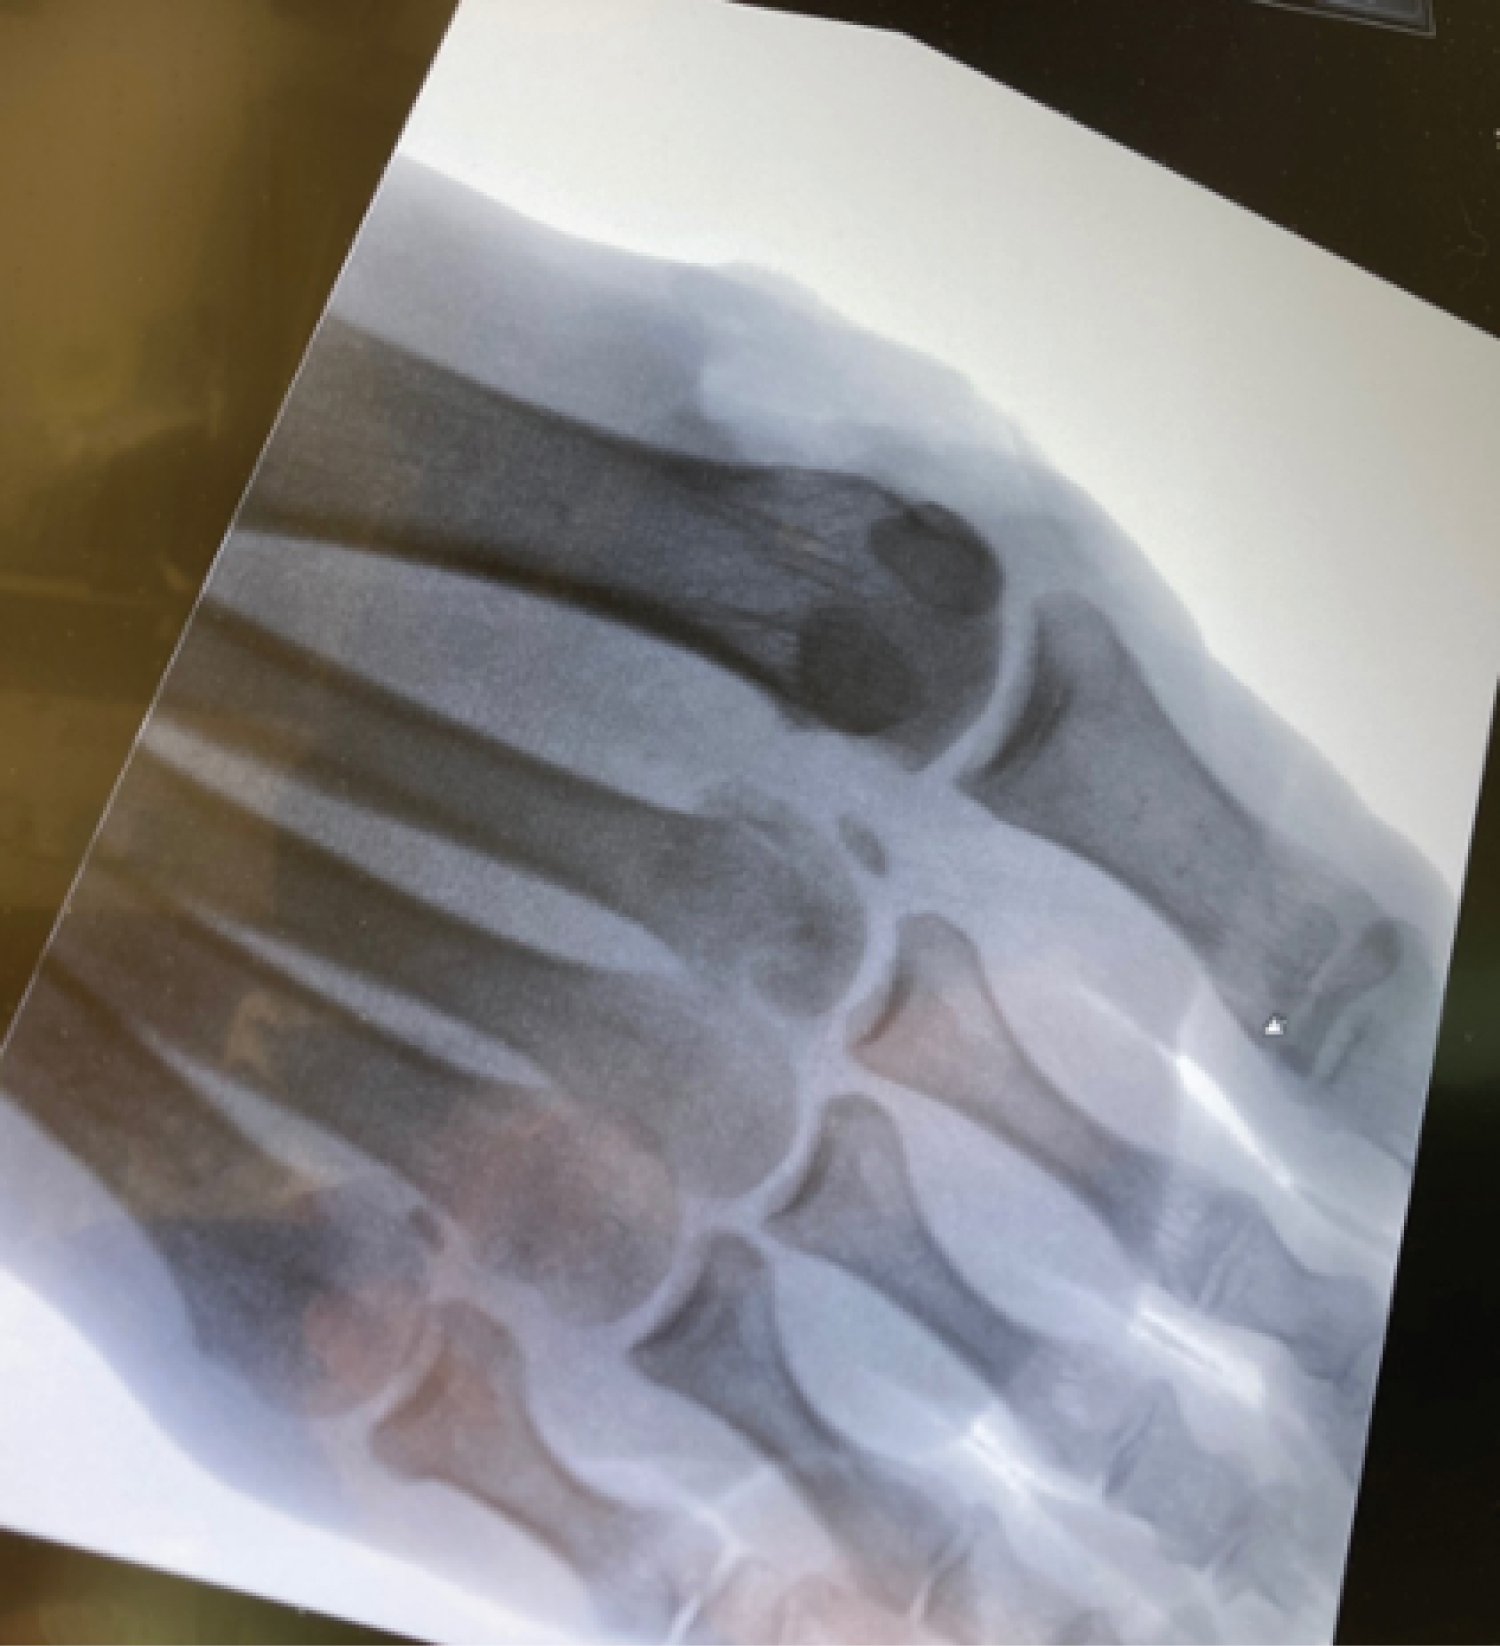

The patient was administered tetanus, cephalexin, and tobramycin in the emergency department. Examination revealed a first MTP dislocation with protrusion of the metatarsal head through the plantar surface of the foot (Figure 1). No motor or sensory deficits were noted. Dislocation of the first MTP joint was confirmed radiographically (Figure 2) and via computed tomography (Figure 3), which also revealed a fracture of the second metatarsal head. Multiple reduction attempts under local anesthesia were performed and failed. The decision was made to proceed to the operating room for open reduction.

Figure 2: AP (A) and lateral (B) of the right foot demonstrating a dorsal first MTP dislocation with medial displacement of the first metatarsal, as well as fracture of the second metatarsal head. View Figure 2